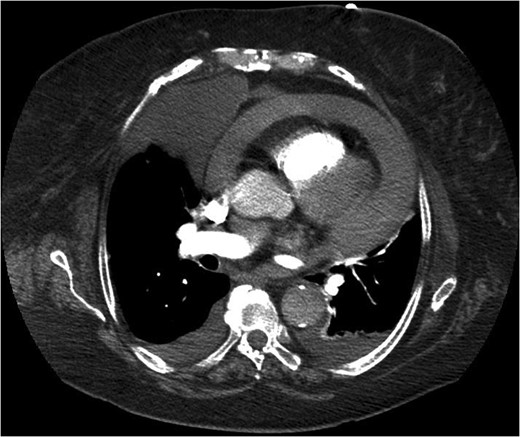

She represented later to our unit with recurrent vomiting. Her investigations revealed a raised lactate and acidosis on arterial blood gas. There was a concern for gastric ischaemia; the decision was taken to proceed to theatre. Given that she was haemodynamically stable with no peritonitis, we chose to operate using a laparoscopic approach. Surgery was performed through four laparoscopy (2 × 11 mm, 2 × 5 mm). A diagnosis of Morgagni hernia was made (Fig. 2). Inside the hernial sac was the transverse colon, the greater curvature of the stomach with a partial gastric volvulus (Fig. 3). The hernia was reduced with the viscera still viable but the sac could not be excised. The defect was repaired with a 6 × 10 cm composite mesh with an absorbable tic fixation on the diaphragm (Fig. 4). No drain was inserted, and the operation time in total was 45 minutes.